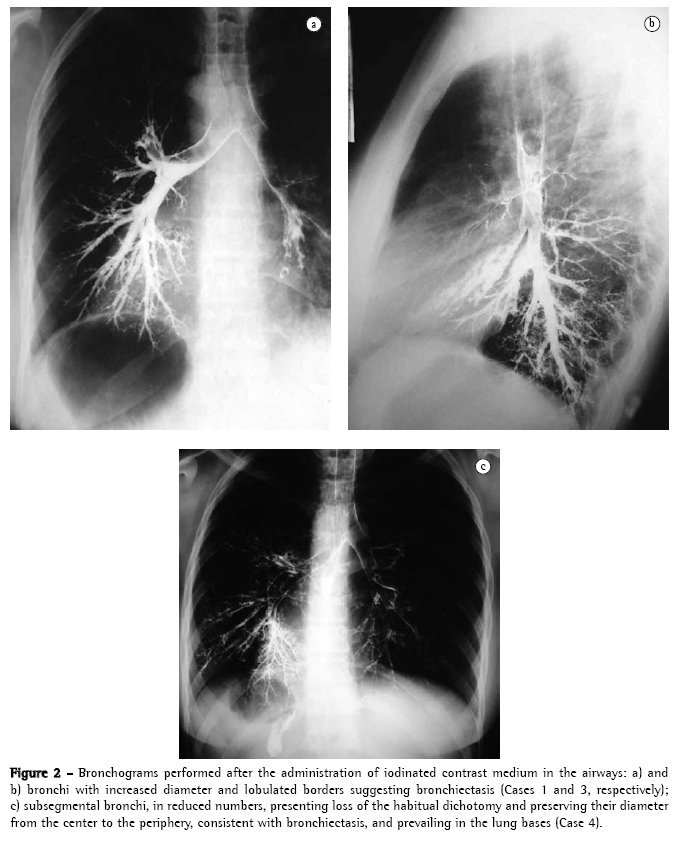

In the first four cases of the series, bronchograms were performed in two phases: first on one side and then, after an interval of approximately thirty days, on the other side. In the last two cases, bronchograms were replaced by high-resolution computed axial tomography. Both tests revealed several types of bronchiectases (cylindrical, cystic, and varicose) that were mainly located in the lower lobes, in the left middle lobe, and in the right lingula due to the situs inversus (Figures 2, 3a, 3b, and 3c).

Of the six patients studied, four underwent bilateral bronchograms, with a thirty-day interval between the X-ray of one side and that the other, naturally prior to the advent of computed tomography.

Despite being universally accepted as the best method for the diagnosis and surgical evaluation of bronchiectasis, bronchogram, initially described by Sicard and Forestier in 1922, has lately been less often employed. This is due to several factors: allergic reactions to the contrast medium; bronchospasm (the procedure causes extreme discomfort to the patient); the test is performed on one lung at a time (the study of the other lung can only be performed after a two- to four-week interval); and difficulty of interpretation by less experienced radiologists. However, the most important factor was the advent, in the 1980s, of computed tomography, which is currently the method of choice for the study of bronchiectasis(19,20) (Figures 3a, 3b, and 3c).